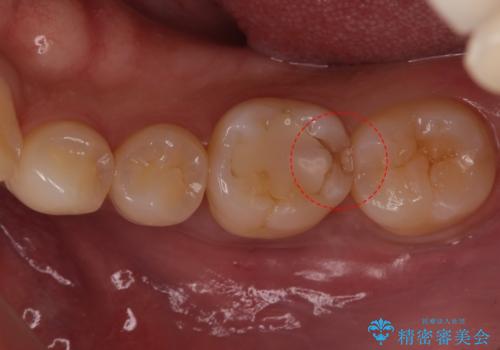

- 右下の奥歯に入れた銀歯を白くしたいとのことで来院されました。

根っこの治療がされていますが、症状もなくレントゲン画像で病変も確認できないため根管内には触れず被せ物のやり替えのみとなりました。

下の奥歯は口を開くと簡単に外から見えてしまいます。